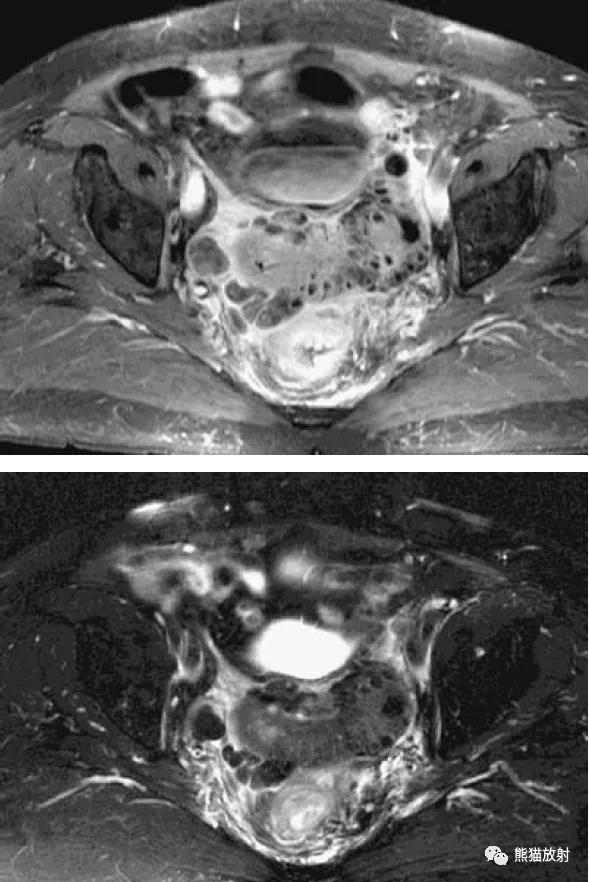

子宫内膜异位症累及子宫直肠陷凹。矢状(A)和横断(B)的T2WI图像显示子宫和直肠之间可见不均质肿瘤(箭头),显示直肠前壁是如何经常被累及。